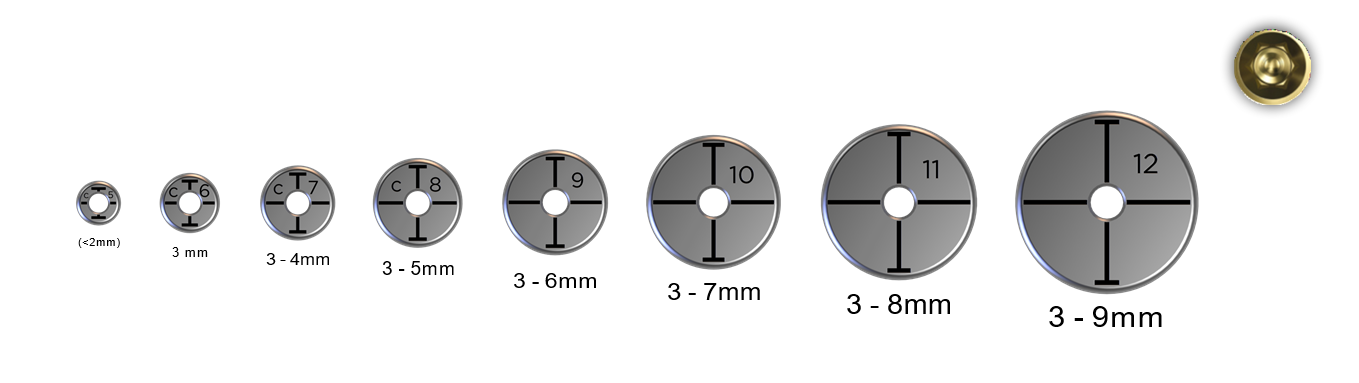

Pasul 1 – Evaluează dimensiunea mezio-distală a spațiului edentat

Evaluarea dimensiunii mezio-distale este importantă pentru a putea identifica dacă spațiul este adecvat pentru a plasa în siguranță un implant.

Evaluarea dimensiunii mezio-distale este importantă pentru a putea identifica dacă spațiul este adecvat pentru a plasa în siguranță un implant.

Această dimensiune se referă, de asemenea, la diametrul maxim al platformei implantului care poate fi plasat în siguranță fără a încălca zona periculoasă. Adică platforma implantului va avea o distanță inter-proximală sigură de cel puțin 1,5 mm față de dinții adiacenți.

Pasul 1 – Utilizează clema cilindrică pentru a perfora și centra osteotomia în spațiul edentat

Fila cilindrică dorită a fost deja descrisă la programarea consultării și fila ideală este cea care se potrivește cel mai bine spațiului edentat fiind în contact ușor cu dinții adiacenți.

Fila cilindrică dorită a fost deja descrisă la programarea consultării și fila ideală este cea care se potrivește cel mai bine spațiului edentat fiind în contact ușor cu dinții adiacenți.

În cazul în care dintele adiacent este absent, atunci idealul este cel cu dimensiuni asemănătoare mezio-distale a dintelui de înlocuit.